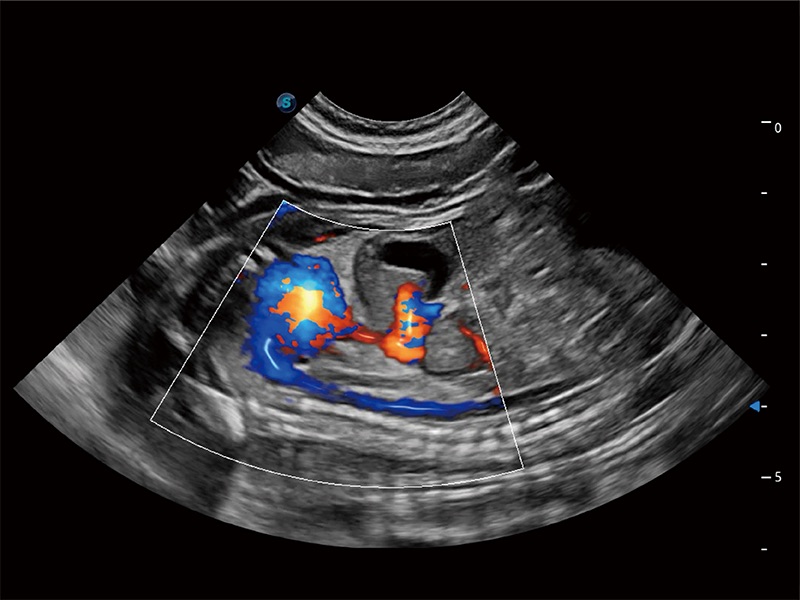

• Bright Flow 立体血流成像

在传统二维血流成像的基础上,呈现血流的立体感,具有动感的生命力之美。即便是微小的血管也能轻松应对,提高了血流的视觉敏感性。

(犬)胎儿主动脉弓立体血流